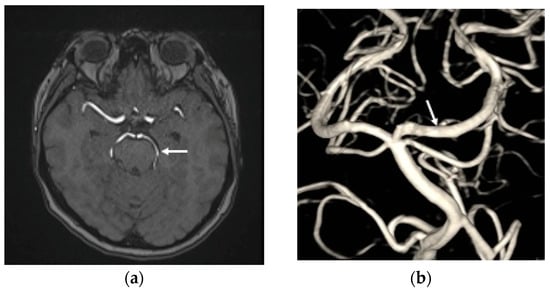

A non-contrast brain computed tomography (CT) scan revealed diffuse subarachnoid hemorrhage (SAH) with a thickness exceeding 1 mm within the basal cistern, predominantly along the left side ambient cistern (Figure 1a). Subsequent CT angiography (CTA) was performed to investigate the etiology of the SAH and demonstrated an irregular vessel contour in the left PCA P2 segment, with a focal arterial pouch consistent with a dissecting aneurysm with a saccular rupture component (Figure 1b). Evaluation of the lumbar spine using CT (Figure 2a) and axial T2-weighted magnetic resonance imaging (MRI) (Figure 2b) revealed an L2 burst fracture with significant spinal canal compromise, resulting in approximately 65% dural sac stenosis. Digital subtraction catheter angiography (DSA) with 3D rotational angiographic acquisition was performed using the Siemens Artis Q angiography system with PURE technology (Siemens Healthineers, Forchheim, Germany). Image reconstruction and aneurysm morphometric quantitative measurements were performed on the Siemens syngo X-Workplace using the syngo 3D Angio (Dyna3D) module. The DSA identified an approximately 5 mm long fusiform dilation along the anterior portion of the left PCA P2 segment (Figure 3a, D1), accompanied by an inferiorly projecting saccular pouch measuring 2.5 mm in diameter (Figure 3a, D2). These findings were diagnostic of a ruptured dissecting aneurysm with a superimposed saccular aneurysm sac (Figure 3a). All cerebrovascular imaging examinations was performed by neuroradiologist Dr. Wu Ming-Ji. A second neuroradiologist Dr. Shen Chao-Yu independently reviewed the images and confirmed the morphometric measurements.

Figure 3.

(a) The digital subtraction catheter angiography (DSA) identified an approximately 5 mm long fusiform dilation (D1, double arrow head) along the anterior portion of the left posterior cerebral artery (PCA) P2 segment, accompanied by an inferiorly projecting saccular pouch measuring 2.5 mm in diameter (D2, single arrow head); (b) the endovascular treatment resulted in near-complete elimination of contrast opacification within the previously visualized dissecting pouch, indicating successful occlusion of the false lumen of the PCA dissection aneurysm (white arrow head).

After multidisciplinary discussion with the neuroradiologists at the Neurovascular Center of Chun Shan Medical University Hospital regarding the prevention of rebleeding from the left PCA dissecting aneurysm, the patient underwent reconstructive endovascular treatment (rEVT) performed by Dr Wu. This intervention was carried out approximately 30 h after the SAH after obtaining informed consent of off-label usage of flow-diverting stent in traumatic cerebral aneurysm from the patient and her family and involved the use of a flow-diverting stents with coiling with significant self-paid expenses. Given the high risk of rebleeding in dissected arteries, along with the potential of in-stent thrombosis and thromboembolic complications following flow-diverting stent deployment, a relatively conservative antiplatelet regimen was selected. The patient received a single loading dose of clopidogrel (Sanofi, Paris, France) 300 mg, administered 8 h before deployment of the device. A Pipeline Flex embolization device (PED Flex device, Medtronic, Irvine, CA, USA) measuring 2.5 mm × 16 mm was positioned across the left PCA P2 segment to reconstruct the parent artery. Subsequently, targeted coil embolization of the saccular pouch in the middle left PCA P2 segment was performed using a stent-assisted coiling technique. The endovascular treatment resulted in near-complete elimination of contrast opacification within the previously visualized dissecting pouch, indicating successful occlusion of the false lumen of the PCA dissection aneurysm (Figure 3b). No immediate procedure-related complications or newly developed neurologic deficits after transarterial embolization (TAE). During the subsequent two weeks after rEVT, the patient exhibited no post SAH sequelae, such as cerebral vasospasm, hydrocephalus, or hyponatremia and maintained antiplatelet therapy with clopidogrel 100 mg daily. The lumbar spinal surgery was performed for L2 burst fracture using a MISS approach without discontinuing antiplatelet therapy. This procedure included left L2 hemilaminectomy for decompression, and percutaneous transpedicle screw fixation from L1 to L3, with preservation of the supraspinous ligament and paraspinal muscle structures.